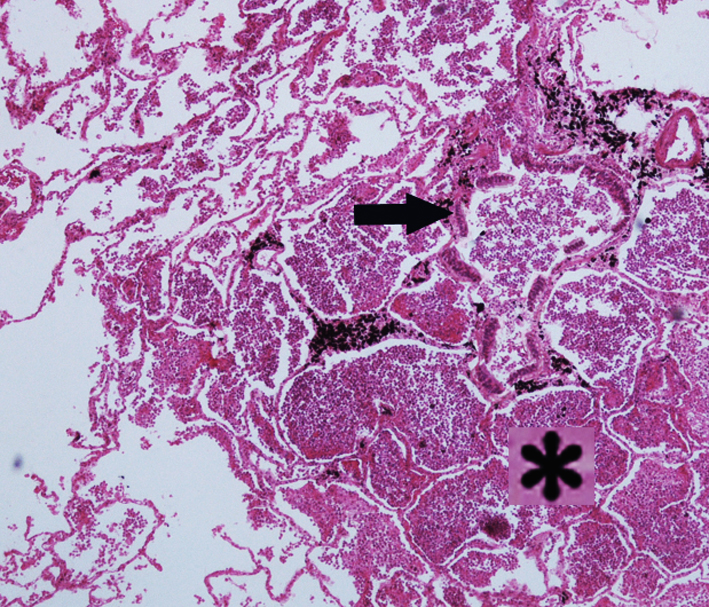

5.Silicosis